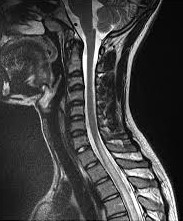

Mielitis Transversa Análisis Clínico y Revisión de Caso

La mielitis transversa es una enfermedad inflamatoria, desmielinizante aguda o subaguda, generalmente monofasica (20% recurrencia)1,2que se desarrolla en ausencia de enfermedad neurológica previa y compromete las vías sensitiva y motora además del control autónomo de la medula espinal.Mujer de 17 años de edad sin enfermedades previas, quien consultó por dificultad para la marcha y disnea. 48 horas de inicio de síntomas, con progresión paulatina. Dolor torácico opresivo en reposo, asociado con disnea de medianos esfuerzos con irradiación retroesternal. Durante la hospitalización presentó disestesias en miembros inferiores que progresan al abdomen, arreflexia en miembros inferiores, nivel sensitivo T4; posteriormente presenta paraparesia, retención urinaria, incontinencia fecal.